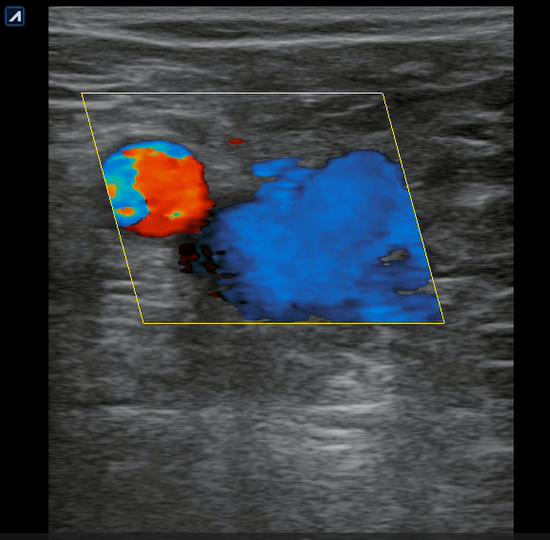

Se realiza ecografía clínica en consulta donde observamos a nivel inguinal adecuada compresibilidad de vena femoral y relleno con Doppler color. Cayado de safena libre y compresible. A 7 cm de distancia del cayado se aprecia, en territorio de safena, dilatación no compresible de la misma, contenido intraluminal ligeramente ecogénico y ausencia de Doppler color compatible con trombosis venosa superficial de 19 cm de distancia. Se estudia recorrido donde se observa en zona de dilataciones varicosas material ecogénico con ausencia de paso de Doppler alternando con zonas de paso parcial. En tercio distal de muslo comienza a desaparecer. Vena femoral profunda, poplítea y perforantes sin datos de trombosis.